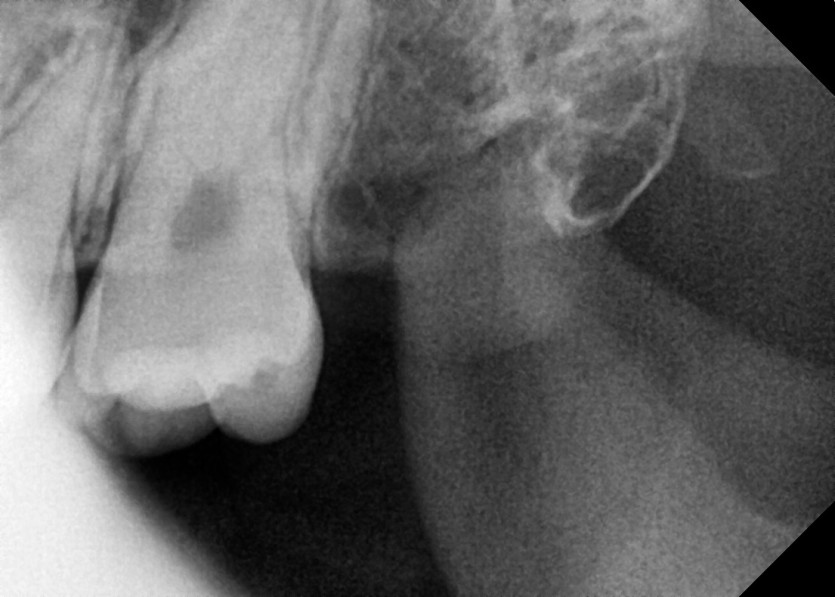

#18,28,38,48 사랑니 발치

구강 외과 전문의가 당일 발치했습니다.